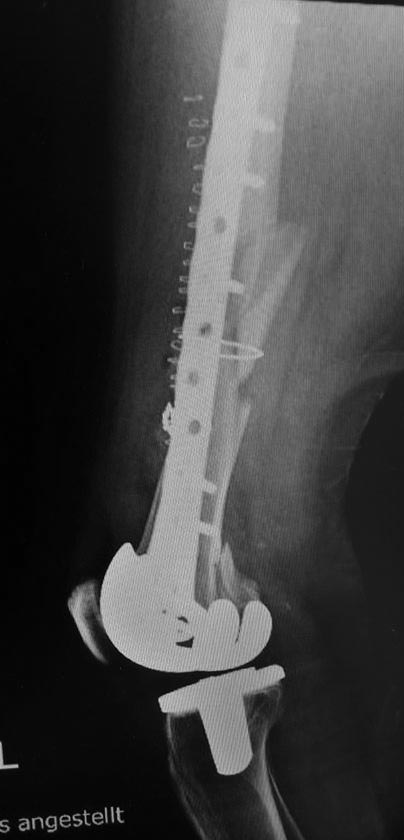

[Ortho] Перипротезный перелом дистального отдела бедра

Как оказалось в нашей ЦРБ сделали уже сегодня шеф решил без СТ. ациент

41 года с большим количеством патологии. То есть полных 76 лет.